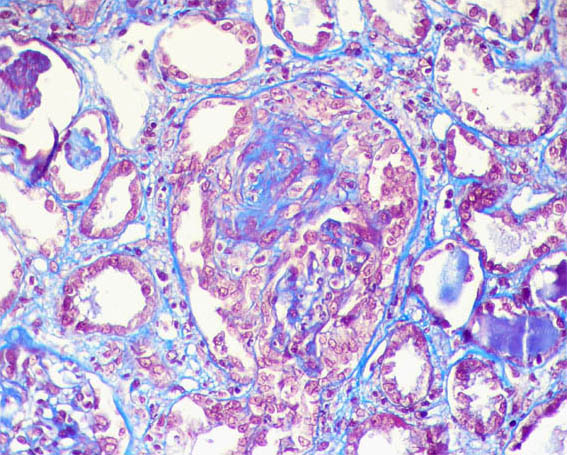

Figure 3. Masson's trichrome staining, X400.

Figure 4.Masson's trichrome staining, X400.